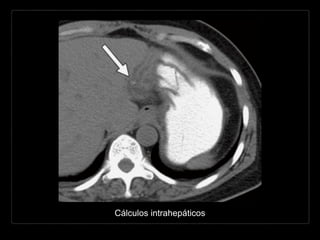

CÁLCULOS INTRAHEPÁTICOS

• raros

• común en pacientes con

colangitis piógena

recurrente

• común en conductos de

calibre mayor

• lóbulo hepático izquierdo

(5x)

Hallazgos por TC y RM

• similares a los de la colédocolitiasis